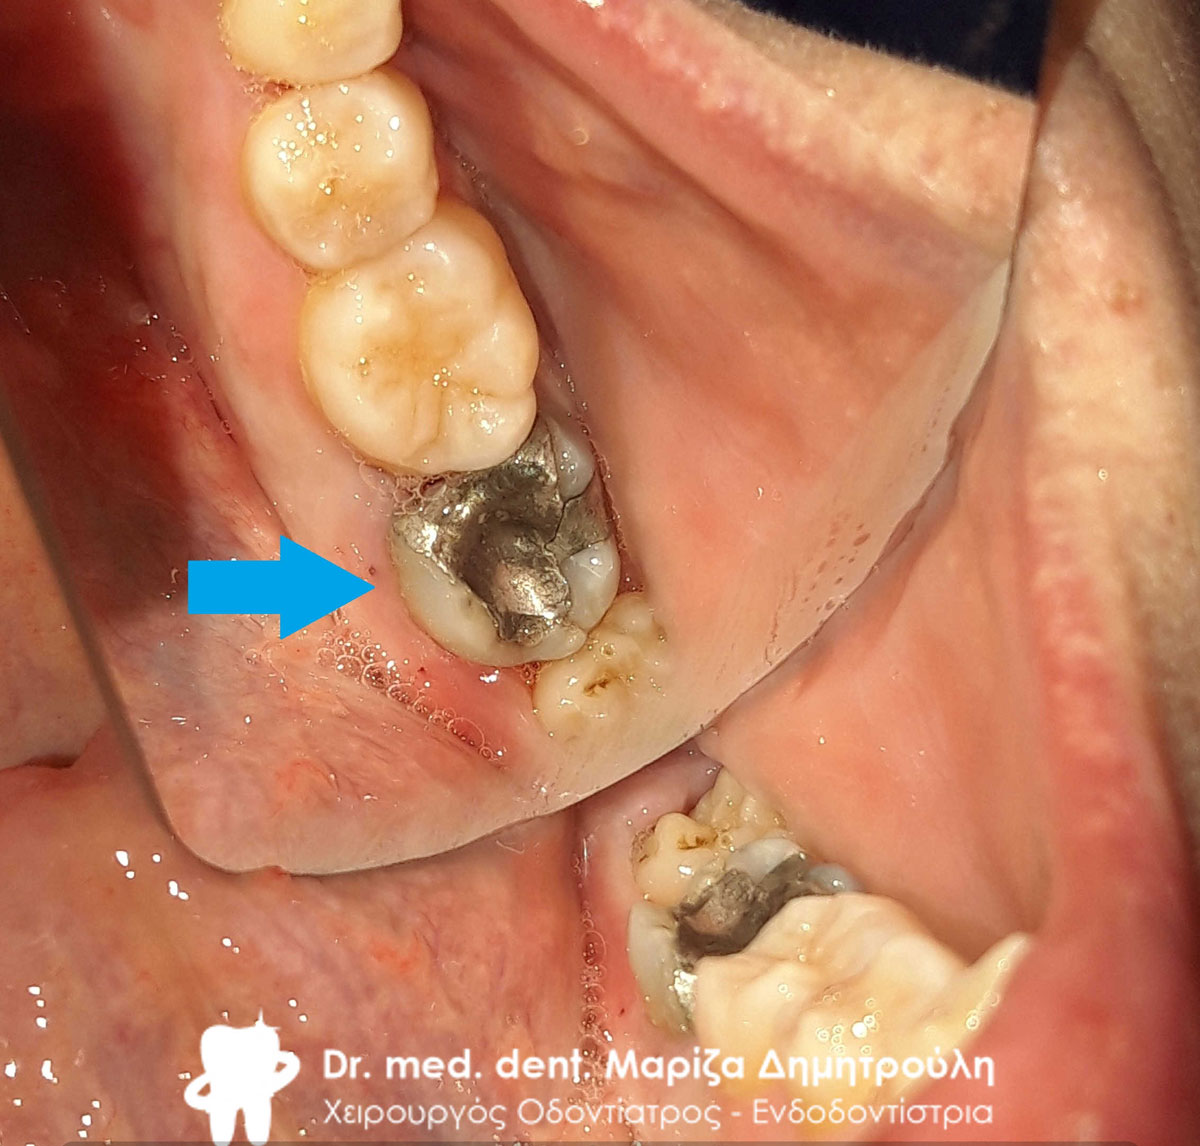

Αρχική κλινική εικόνα του ήδη απονευρωμένου πρώτου γομφίου

Εικόνα της παλιάς απονεύρωσης αμέσως μετά τη διάνοιξη του πρώτου γομφίου